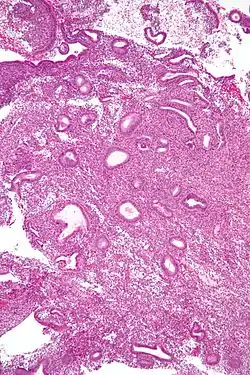

Die einfache Hyperplasie besteht aus zystisch erweiterten Schleimhautdrüsen (Schweizer-Käse-Muster) mit reichlich Bindegewebe (Stroma) zwischen den Drüsen.

Die komplexe Hyperplasie ist durch eine Zunahme des Drüsen-Stroma-Verhältnis gekennzeichnet. Außerdem sind die Drüsen durch Aufzweigungen und Knospungen unregelmäßiger gestaltet.

Die atypische Hyperplasie weist zusätzlich zu den Veränderungen der Gewebsarchitektur Veränderungen auf zellulärer Ebene auf: abgerundete, blasse Zellkerne, große Nucleoli.